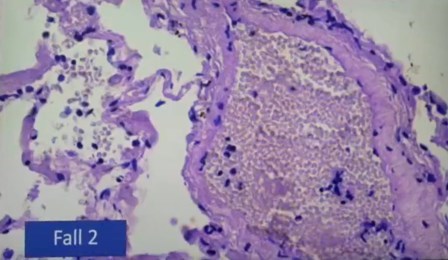

Eritrocitos grumos

Eritrocitos normales, separados

Otro caso de eritrocitos en grumos en inflamación de vena pulmonar

Caso severo, linfocitos en pared vascular

Infarto pulmonar que no debería ser mortal, se ven los linfocitos